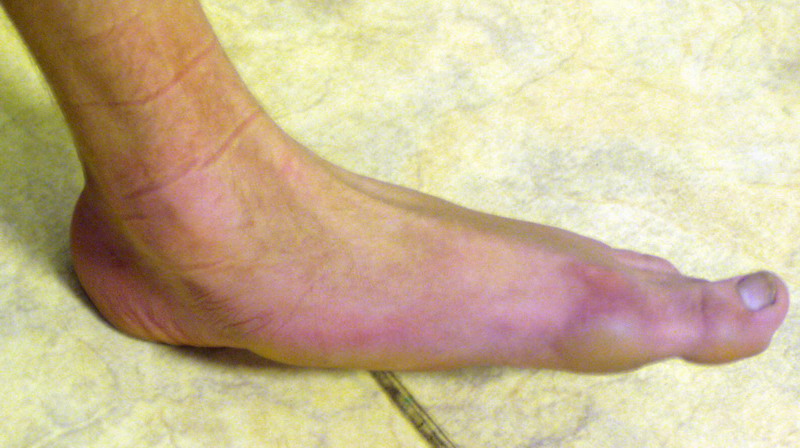

Пациент 15 л., болезнь Литтля, спастический нижний парапарез, интеллект высокий. Ребенок настроен на активный образ жизни. С недавнего времени начал ходить без дополнительной опоры. Появилась проблема с левой стопой - во время ходьбы опора приходится на смещенную кнутри таранную кость.

Может образоваться болезненный натоптыш или язва.Общепринятой операцией является трехсуставной артроде с мобилизацией таранной кости. Выполнять такую операцию у спастика и в раннем возрасте проблематично. Родстьвенники тем более готовы материально и морально осуществить хирургическое лечение за рубежом, если оно показано и возможно.Предпочтительно в Австрии и Германии. Если кто-то посоветует координаты таких клиник - были бы признательны.

Это типичная проблема со стопами у больных спастическим церебральным параличом. У Вашего пациента ситуация несколько запущена. Но решать её надо.

В приводимом случае, 15 летнему больному показан 3-суставной артродез. Однако считаю нецелесообразным существенно менять конфигурацию стопы, поскольку плоско-вальгусные деформации стоп это компенсаторный ответ на сгибательно-приводящие установки нижних конечностей. Изменение положения стоп(коррекция пронации) может нарушить сложившийся стереотип ходьбы, и ухудшить ситуацию.